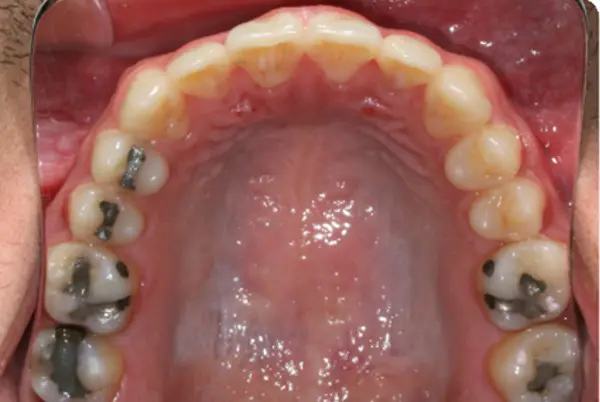

Before

After